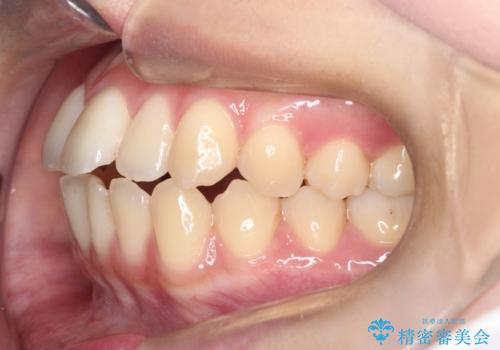

- 前歯のガタガタ(叢生)と、前歯が出ている(突出している)ことを気にされてご来院されました。精密な検査の結果、歯が並ぶスペースと、前歯を引っ込めるスペースの両方が不足していると診断。患者様のご希望に合わせ、透明で目立ちにくいインビザライン(マウスピース矯正)による治療計画を立案しました。スペースの確保は、奥歯全体を奥へ動かす遠心移動と、歯の側面をわずかに削る**IPR(歯間乳頭保護下ストリッピング)**を組み合わせて行い、前歯を効果的に引っ込めることを目指します。

今回の矯正治療では、透明なマウスピース型の装置インビザラインを使用しました。前歯を無理なく引っ込めるスペースを作るため、まず奥歯全体を後方へ移動させる遠心移動を実施。さらに、安全性が確保できる範囲で歯の側面をわずかに削るIPRを併用し、必要なスペースを確保しました。これらの処置により、前歯のデコボコが解消され、前に出ていた前歯も適切に引っ込みました。目立たない装置で治療を完結することで、叢生と突出感が解消され、機能性と審美性が向上した美しい口元を獲得していただけました。